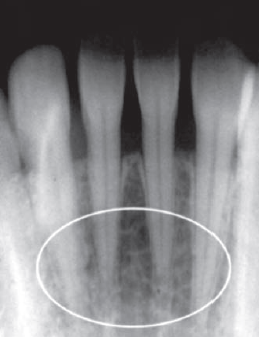

46. What is showing by arrow?

Genial Tubercles (Mental Spine) bony protuberances located on the lingual surface of the mandible slightly above the inferior border and in the midline. serve to attach the genioglossus muscles (at the superior tubercles) and the geniohyoid muscles (at the inferior tubercles) to the mandible. Usually well visualized on mandibular occlusal radiographs as one or more small projections.